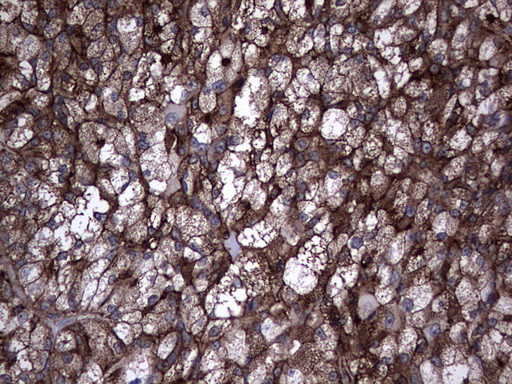

TG Antibody in Immunohistochemistry (Paraffin) (IHC (P))

TG Antibody (CF804409) in IHC (P)

Immunohistochemical staining of paraffin-embedded Carcinoma of Human thyroid tissue using anti-TG mouse monoclonal antibody. (Heat-induced epitope retrieval by 1 mM EDTA in 10mM Tris, pH8.5, 120°C for 3min, TA804409) {{ $ctrl.currentElement.advancedVerification.fullName }} 验证信息 View more